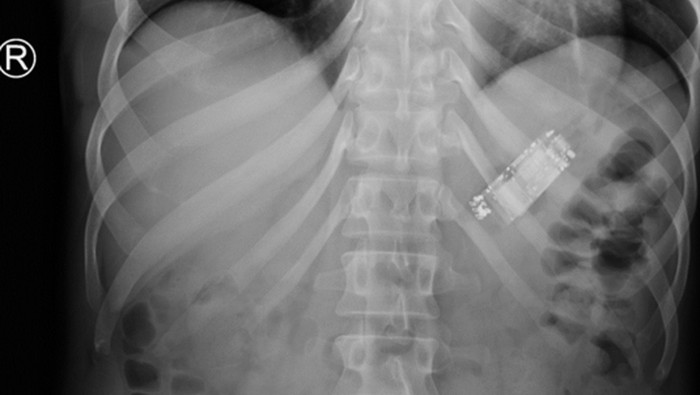

Seorang narapidana 44 tahun dilarikan ke rumah sakit setelah mengaku menelan sebuah ponsel kecil. Ia sempat menahan nyeri perut ringan selama hampir dua minggu sebelum akhirnya mencari pertolongan. (Foto: Cureus Journal)